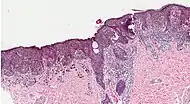

Histopathologic types

SN TypeFeaturesIncidence[82][notes 1]PhotographMicrograph

1. Superficial spreading melanoma Melanoma cells with nest formation along the dermo-epidermal junction. 70%

2. Nodular melanoma Grows relatively more in depth than in width. 15% - 20%

3. Lentigo maligna melanoma Linear spread of atypical epidermal melanocytes as well as invasion into the dermis.[83] 5% - 10%

4. Acral lentiginous melanoma Continuous proliferation of atypical melanocytes at the dermoepidermal junction.[84] 7% - 10%